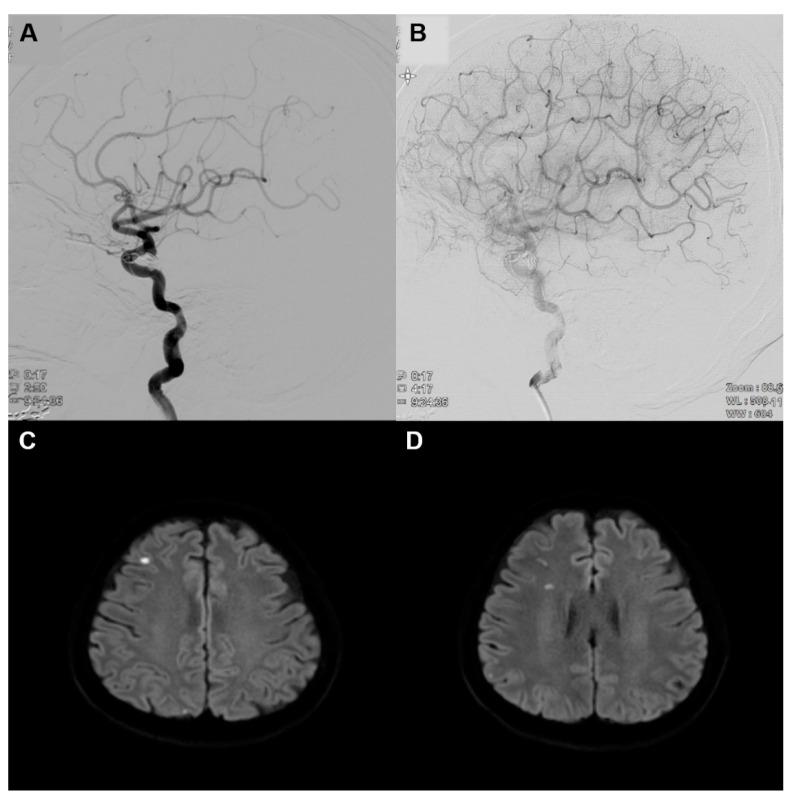

Transfemoral cerebral angiography (TFCA) has been increasingly used as diagnostic method for the evaluation of cerebral vessels. Ophthalmologic complication after TFCA has rarely been reported, and most complications are associated with an intraoperative thrombo-embolic event. We reported a patient who developed a superior altitudinal visual field defect one day after diagnostic TFCA. The ophthalmic exam revealed a prominent inferior optic disc edema, and the fluorescein angiographic showed the non-perfusion of the corresponding inferior sectoral optic disc. Diffusion-weighted MRI on the day following cerebral angiography revealed multiple focal scattered acute infarctions. Even one month after steroid pulse therapy, the superior nasal field defect remained with minimal improvement. We believe this case was consistent with an acute anterior ischemic optic neuropathy (AION) due to thrombo-embolism after TFCA. Ophthalmic examinations and a visual field test should be performed before and immediately after the TFCA, particularly in the case with a high risk of thromboembolic events.

经股动脉脑血管造影术(TFCA)已越来越多地被用作评估脑血管的诊断方法。TFCA术后的眼科并发症鲜有报道,且大多数并发症与术中血栓栓塞事件有关。我们报告了1例患者,在诊断性TFCA术后1天出现上半视野缺损。眼科检查发现视盘下方明显水肿,荧光素血管造影显示相应的视盘下方扇形区域无灌注。脑血管造影术后当天的弥散加权磁共振成像显示多发局灶性散在急性梗死灶。即使在进行类固醇脉冲治疗1个月后,鼻上视野缺损仍存在,仅略有改善。我们认为该病例符合TFCA术后血栓栓塞所致的急性前部缺血性视神经病变(AION)。在TFCA术前及术后应立即进行眼科检查和视野测试,尤其是在血栓栓塞事件风险较高的情况下。